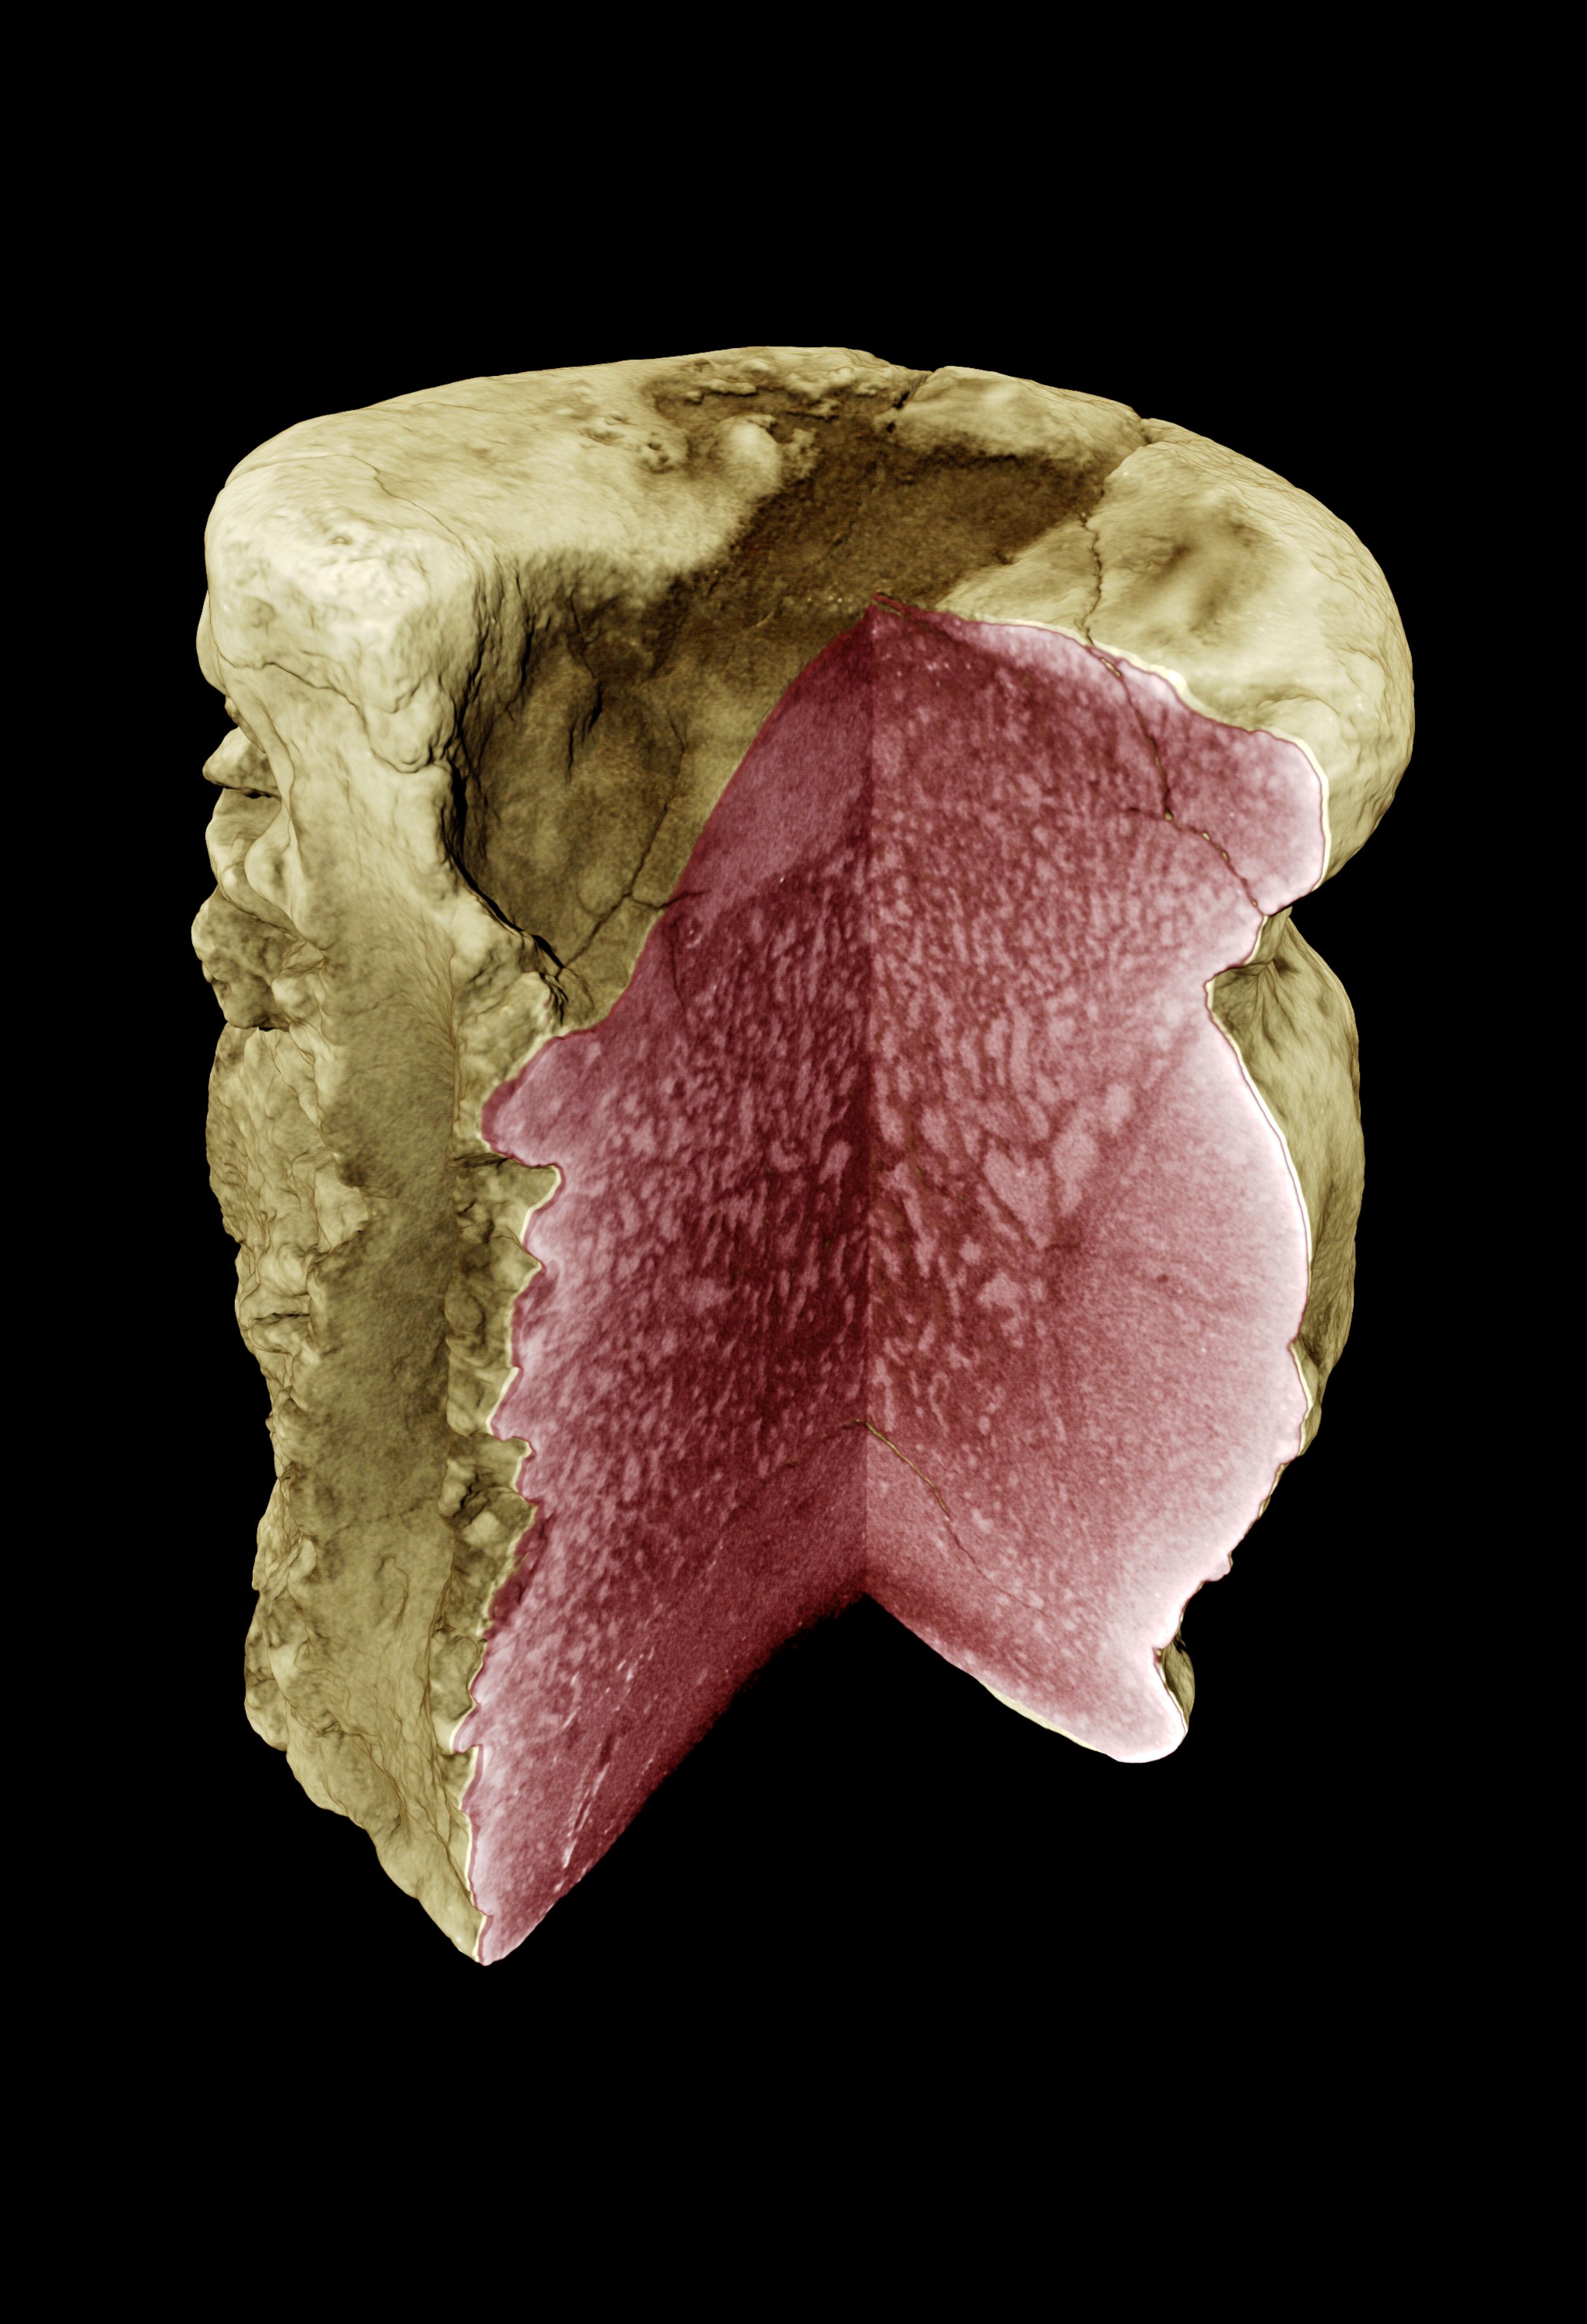

Krankhafte Strukturveränderungen in einem Dinosaurierknochen<br />sichtbar gemacht mit Synchrotron-Holotomografie<br />

Krankhafte Strukturveränderungen in einem Dinosaurierknochen

sichtbar gemacht mit Synchrotron-Holotomografie

© F. Wieder, A. Hilger, HZB

Für die dreidimensionalen Untersuchungen setzten Dr. Ingo Manke und sein Team am Institut für Angewandte Materialforschung des HZB unter anderem die Synchrotron-Holotomografie ein, die sie am Elektronenspeicherring BESSY II des HZB aufgebaut haben. Diese Technik erlaubt dreidimensionale Abbildungen mit besonders hohem Kontrast und hoher Ortsauflösung.

In der tomografischen Aufnahme offenbart der fossile Wirbel das charakteristische radiologische Erscheinungsbild der Paget-Krankheit: Knochenabbau im inneren Bereich des Wirbels und Knochenanbau im äußeren Bereich, der zu einer Verdickung der Außenschicht führt.